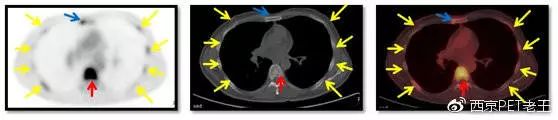

我们又把CT调整到骨窗,看骨骼病变的情况,可以看到全身绝大部分骨骼都有转移,但骨质结构破坏不明显(中列),说明这种是早期的骨转移,如下图:

红色箭头:胸椎及附件转移;黄色:肋骨转移;绿色:肩胛骨转移;蓝色:锁骨胸骨端转移

红色箭头:胸椎转移;黄色:肋骨转移;蓝色:胸骨转移